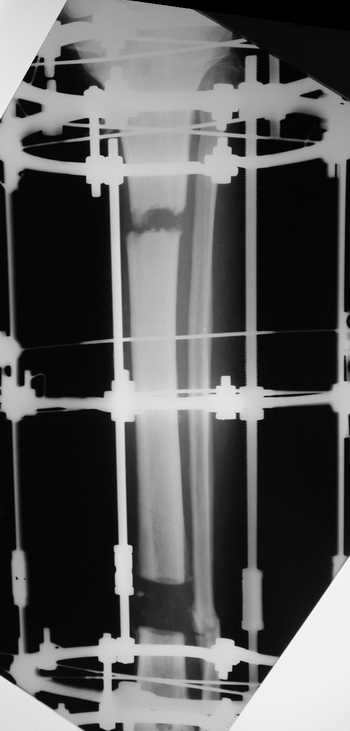

Женщина 46 лет, неудачно лечившаяся по поводу перелома голени в нижней 1\3 сначала в гипсе, поступила через 6 месяцев после остеосинтеза пластиной (рис 1). Имелась деформация в нижней 1\3 голени: варус, антекурвация, наружная ротация, два свища. Удалена пластина, дебридмент мягких тканей,

остеотомия м\б кости, аппарат Илизарова. По рентгенограммам в двух проекциях произведено планирование устранения смещений (рис 2 и 3), между вторым и третьим кольцом установлены 6 телескопических дистракторов Гесапода, данные введены в программу, и далее втечение 10 дней больная подкручивала телескопы согласно выданной компьютером инструкции. По завершению репозиции гексаподные телескопы обратно заменены на обычные штанги от аппарата Илизарова (рис 4 и 5). Еще через две недели забит гвоздь (рис 6, контроль

через 4 месяца).